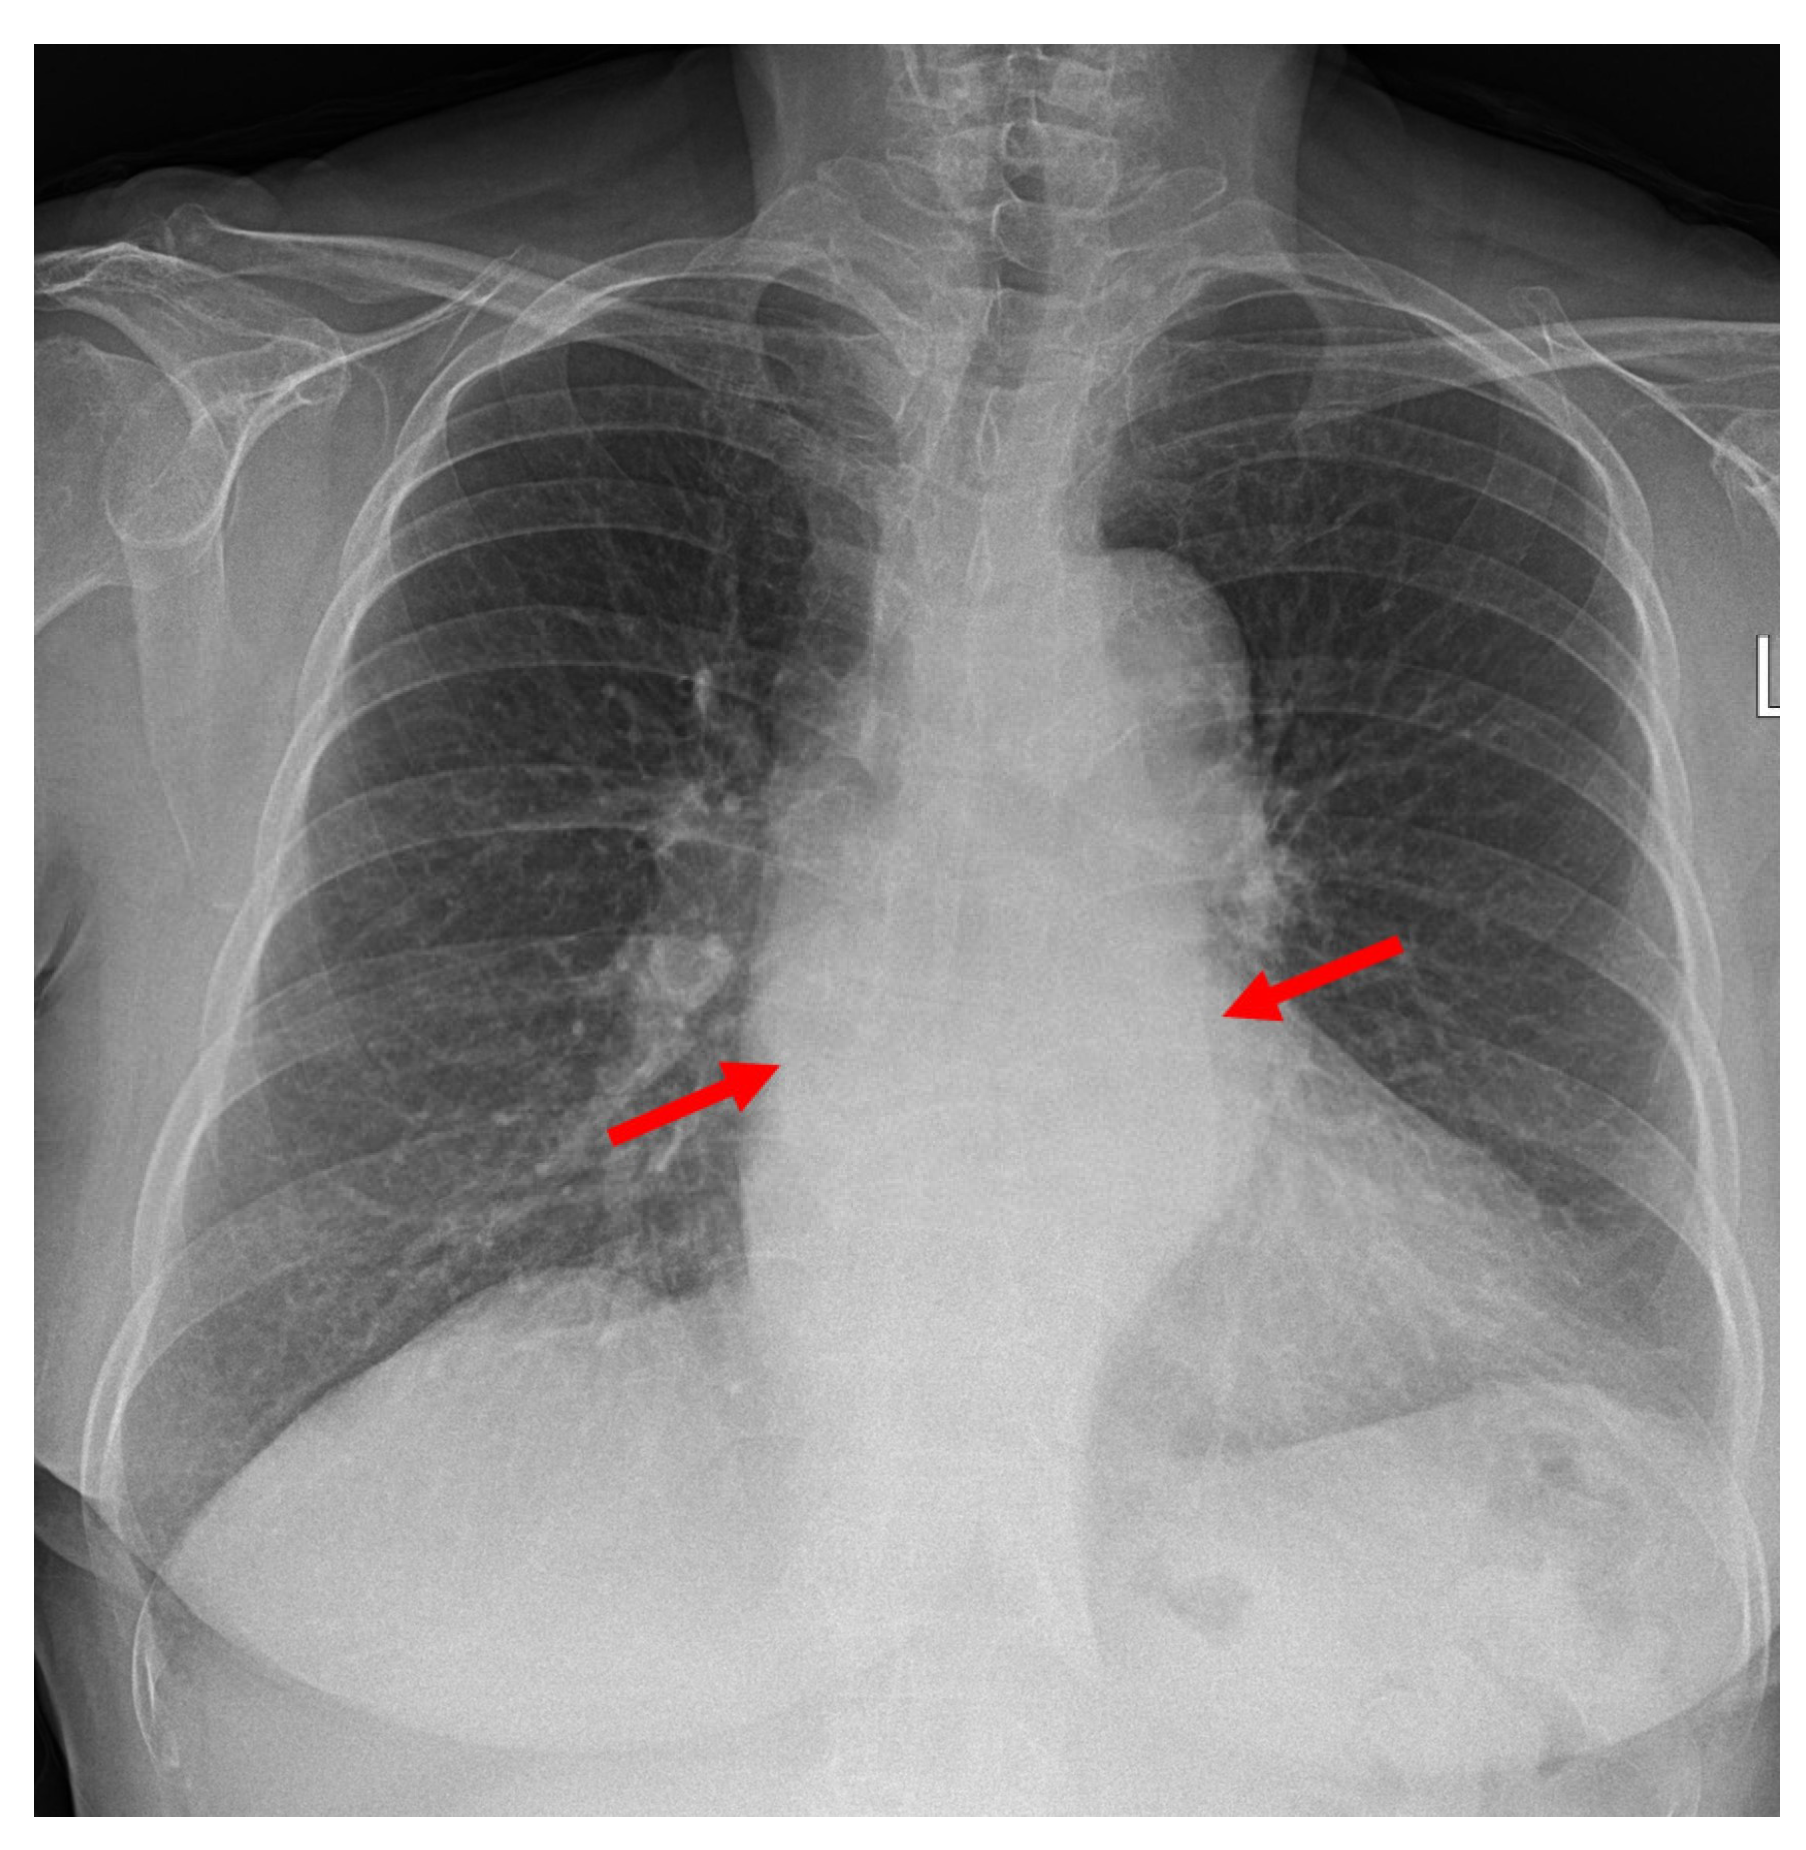

2. Detailed Case Description